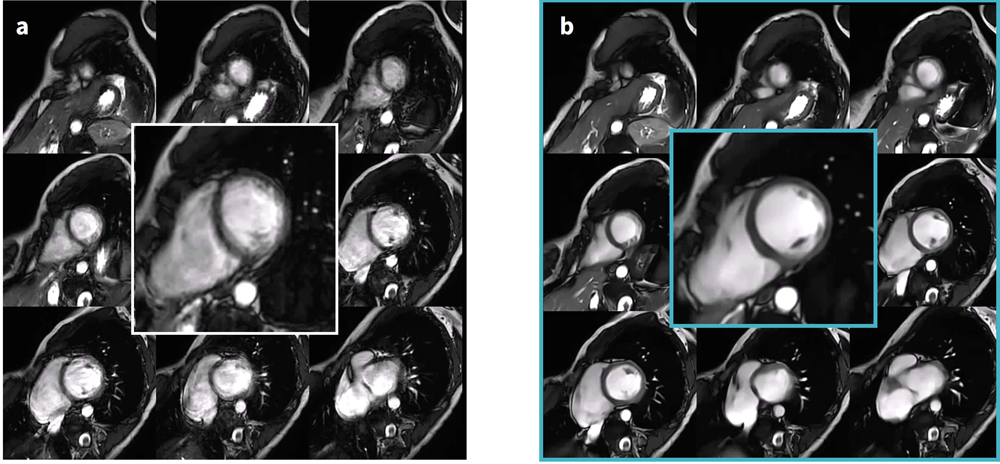

不整脈患者への対応

通常,心室性や上室性期外収縮が散発する程度では,従来の撮像法でも著しく画質が劣化することはない。一方,頻発する期外収縮や心房細動でR-R間隔が不整な場合,従来のCine撮像ではアーチファクトにより画質が顕著に低下する(Figure.2-a)。

Sonic DL™ では,高いアクセラレーションファクターを設定することで,1心拍での撮像が可能である。心拍を跨がず一回の心拍でCineを撮り切ることにより,R-R間隔が一定でない不整脈や呼吸制御が困難な症例でも,アーチファクトの少ない画像を取得することが可能である(Figure.2-b)。

SonicDL_Iwateikadai04.jpg

Figure.2 心室性期外収縮頻発、呼吸制御困難症例

a) 従来法 Acceleration factor 2 (ASSET), 15sec x 9 breath hold (9slice)

b) Sonic DL™ Acceleration factor 10(Sonic DL™), 17sec x 1breath hold (9slice)

Sonic DL™ を使用して1心拍撮像を行うことによって、期外収縮に伴うモーションアーチファクトが抑制されている。